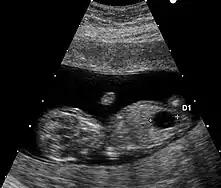

Le marqueur échographique utilisé est la clarté nucale. La technique de mesure doit répondre à des critères stricts.

Il existe un autre marqueur échographique mais de mesure plus délicate : l'os propre du nez.

Échographie

Aucun signe échographique n'est symptomatique de la trisomie 21. Néanmoins, un certain nombre d'anomalies mineures ou majeures qui se rencontrent plus fréquemment dans cette maladie chromosomique peuvent être mis en évidence.

- Anomalies mineures

- hypoplasie ou absence des os propres du nez ;

- fémur court, inférieur au 5e centile pour l'âge ;

- épaisseur de nuque supérieure à 6 mm à 20 semaines ;

- écartement important entre les premier et deuxième orteils ;

- brièveté de la deuxième phalange du cinquième doigt (brachymésophalangie) ;

- langue protruse…

- Anomalies majeures

- des malformations cardiaques (canal atrio-ventriculaire et en particulier) (dans 40 % des cas) ;

- des sténoses digestives (dans 10 à 18 % des cas) (image en « double bulle » de sténose duodénale).